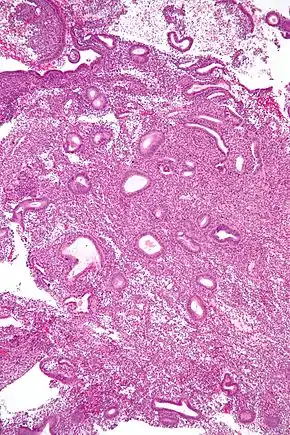

Micrograph showing an endometrial biopsy with simple endometrial hyperplasia, where the gland-to-stroma ratio is preserved but the glands have an irregular shape and/or are dilated. H&E stain.